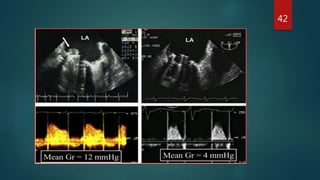

St. Jude mitral prosthesis is demonstrated. A: During

systole, the hemidisks are shown in the closed position

(arrows). B: During diastole, the two disks are recorded

in the open position (arrows).

Starr-Edwards mitral prosthesis is shown. A: During

systole, the poppet is seated within the sewing ring

(arrows). B: During diastole, the poppet moves forward

into the cage (arrows), allowing blood flow around the

occluder.

St. Jude mitralprosthesis is demonstrated. A: During systole, the hemidisks are shown in the closed position (arrows). B: During diastole, the two disks are recorded in the open position (arrows). Starr-Edwards mitral prosthesis is shown. A: During systole, the poppet is seated within the sewing ring (arrows). B: During diastole, the poppet moves forward into the cage (arrows), allowing blood flow around the occluder. 20